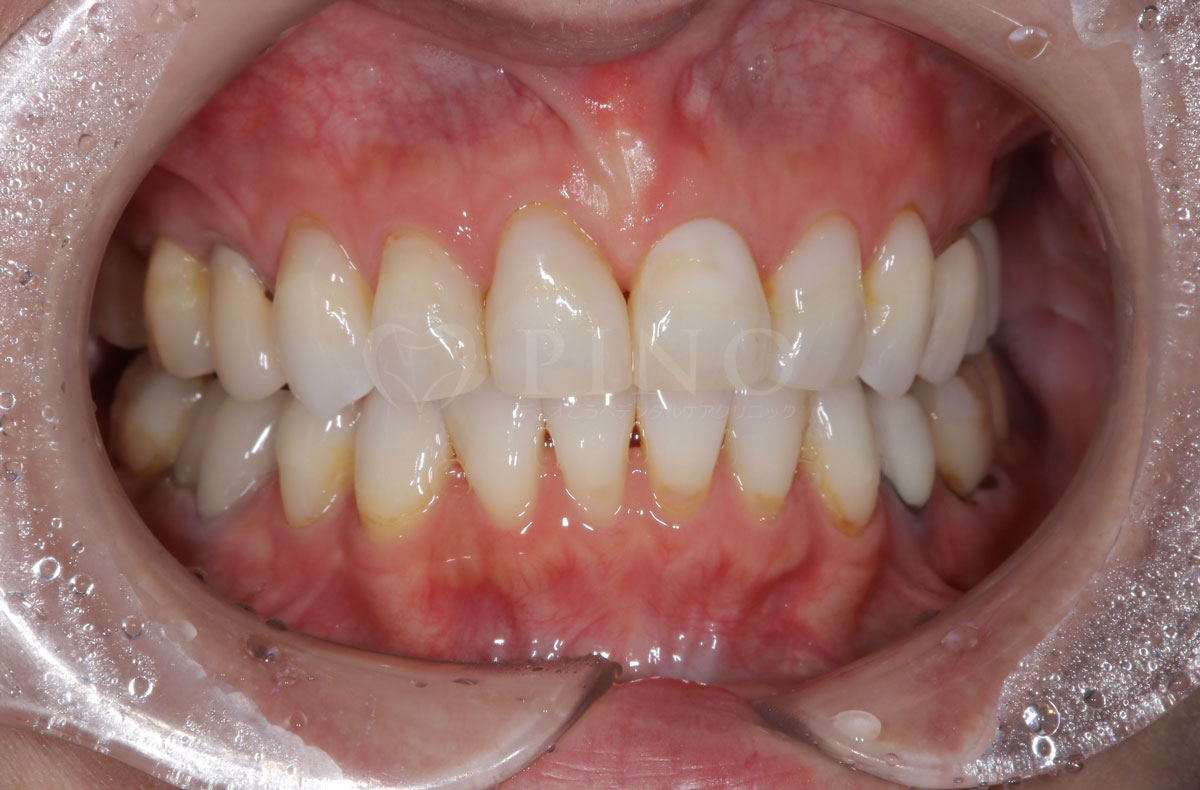

症例12:噛み合わせが深く、下の歯が見えないのが気になる(20代男性)

主訴 噛み合わせが深く、下の歯が見えないのが気になる 診断名 過蓋咬合(かがいこうごう)、顎関節後方転位 治療方法 マウスピース矯正、補綴治療(被せ物、詰め物の治療) 抜歯 なし オルソパルス あり 治療期間 2年 費用 746,000円 + 165,000円(オルソパルス)+ 補綴費用(保険診療) 副作用・注意点 矯正後の後戻りを防ぐためリテーナーの使用が必要となる、詰め物の変色が起こる可能性がある 備考 下顎の位置を正しい位置にするためにスプリントを使用した。ホワイトニングも併用。